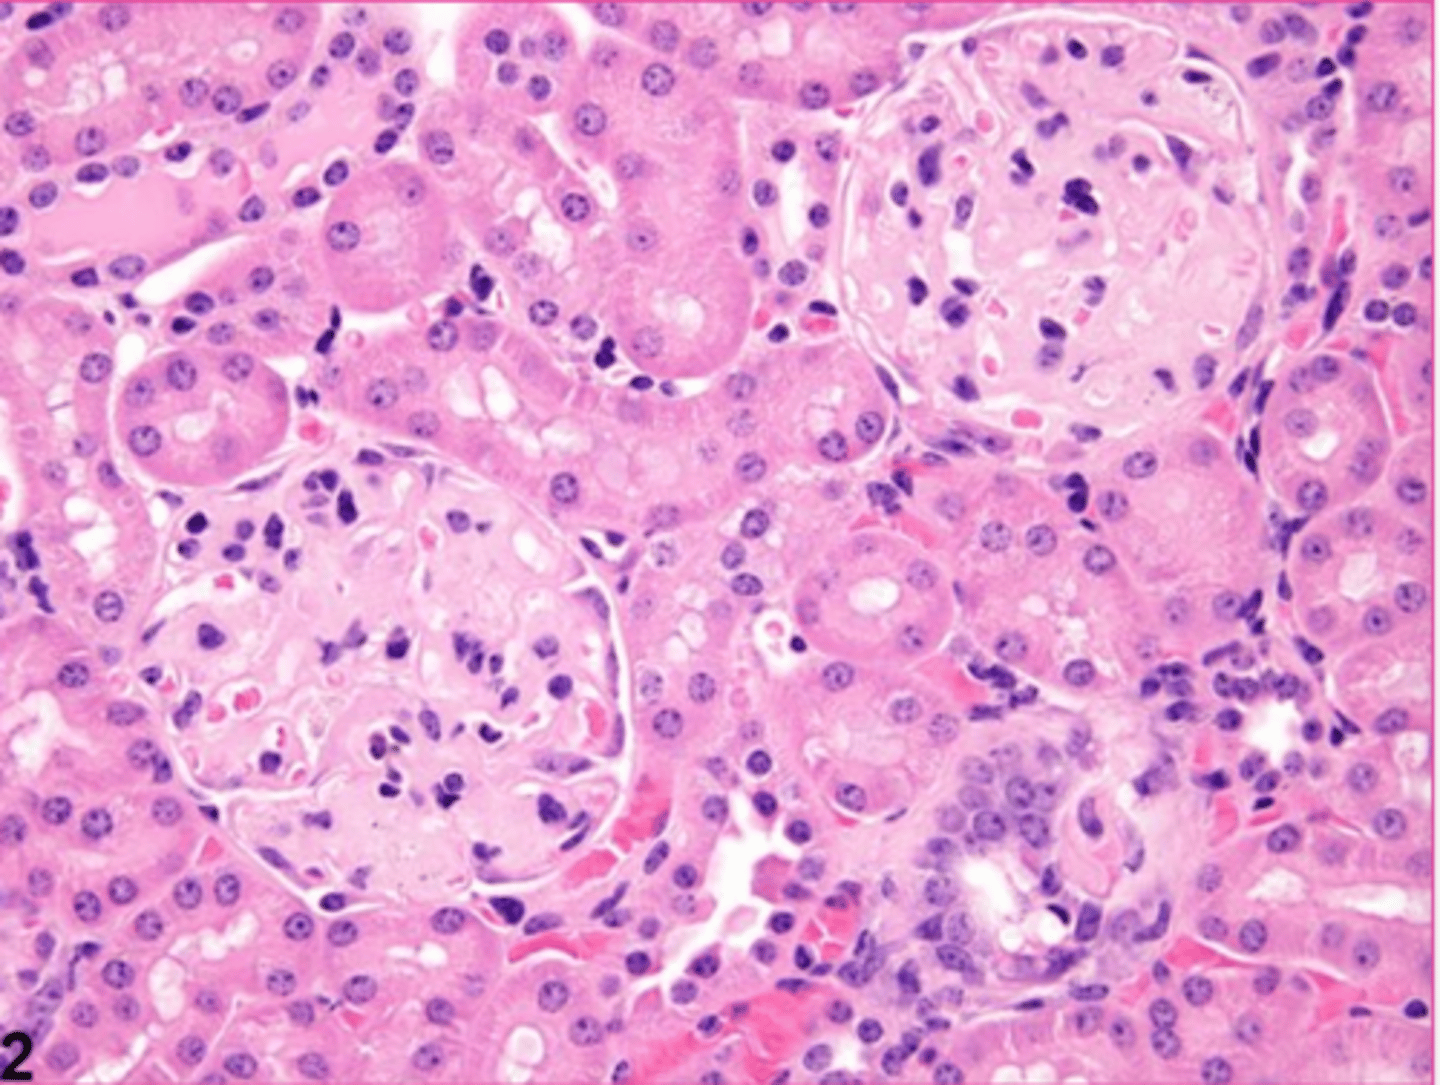

amyloid

describe the extracellular inclusion

<p>describe the extracellular inclusion</p>